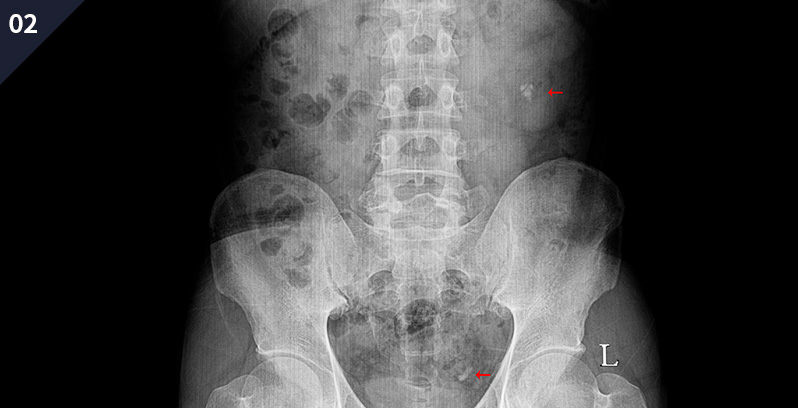

¿ä·Î°á¼®ÀÇ ¿©ºÎ ¹× À§Ä¡¸¦ ÆÄ¾ÇÇÏ´Â